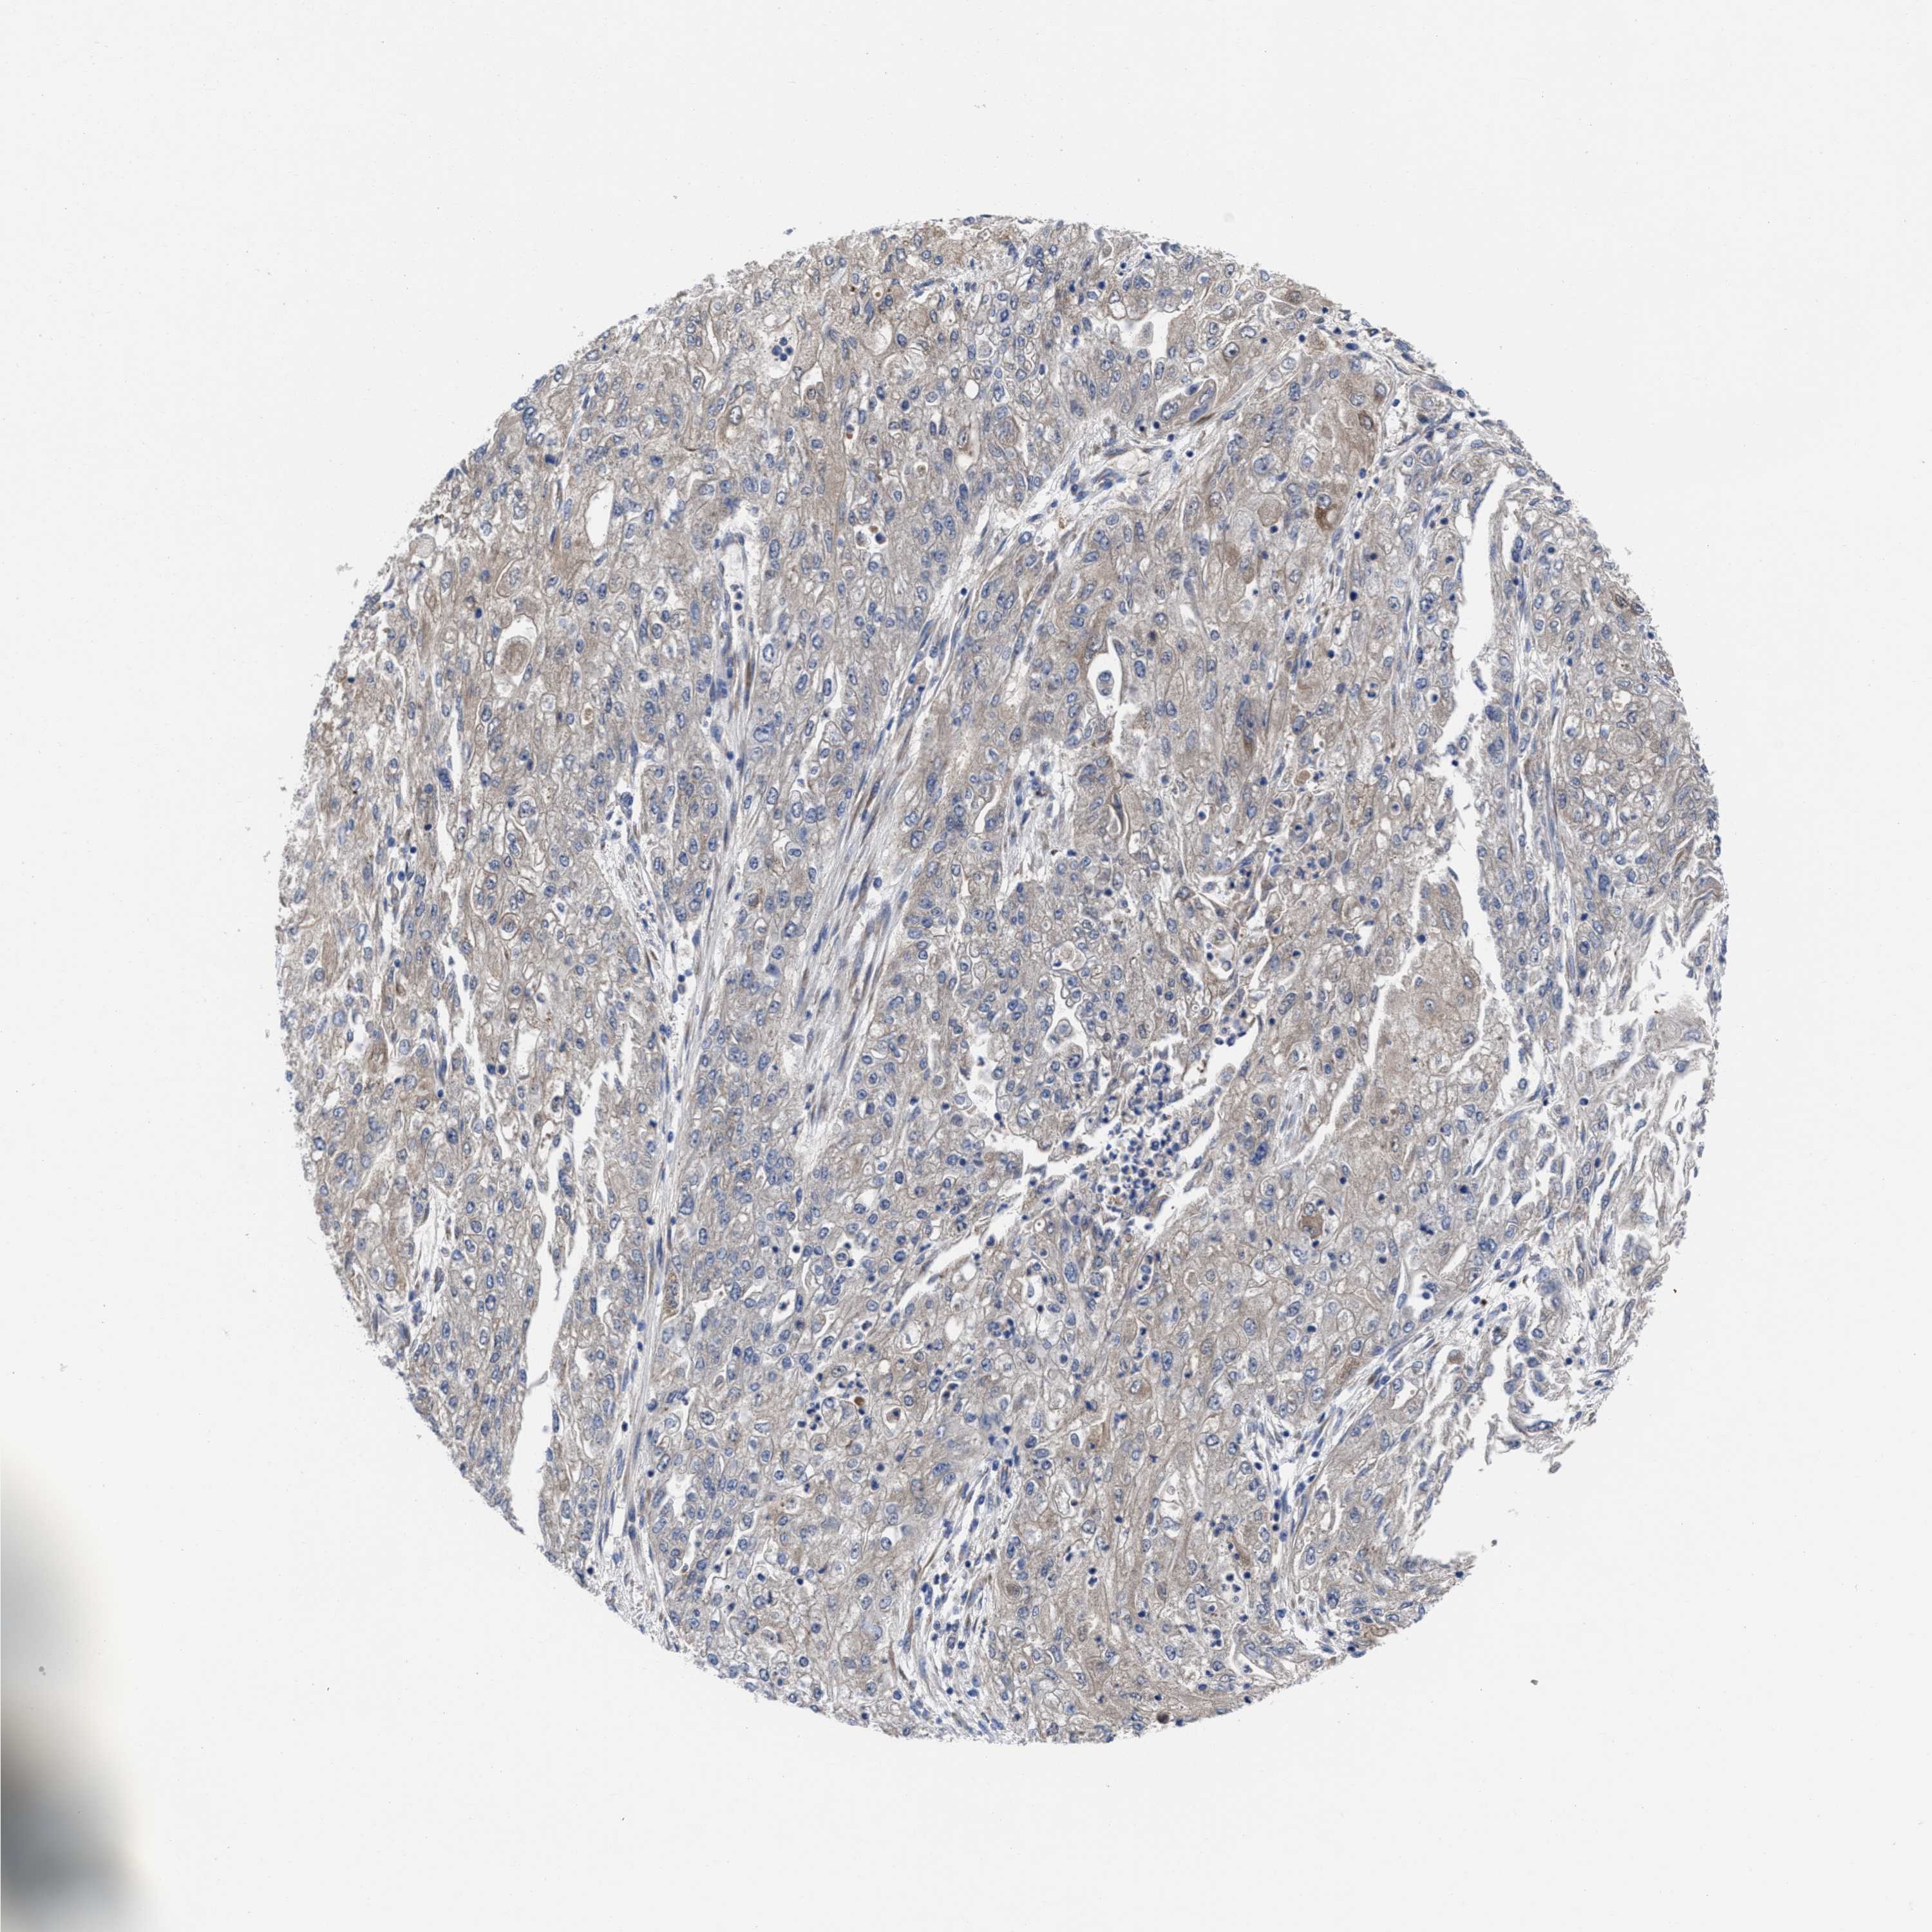

ENDOMETRIAL CANCER - Protein expressioni

A mouse-over function shows sample information and annotation data. Click on an image to view it in a full screen mode. Samples can be filtered based on level of antibody staining by selecting one or several of the following categories: high, medium, low and not detected. The assay and annotation is described here.

Note that samples used for immunohistochemistry by the Human Protein Atlas do not correspond to samples in the TCGA dataset.

Antibody stainingi

Antibody staining in the annotated cell types in the current human tissue is reported as not detected, low, medium, or high, based on conventional immunohistochemistry profiling in selected tissues. This score is based on the combination of the staining intensity and fraction of stained cells.

Each image is clickable and will lead to virtual microscopy that enables deeper exploration of all samples and also displays staining intensity scores, fraction scores and subcellular localization as well as patient and tissue information for each sample.

Antibody HPA022931

Staining

High

Medium

Low

Not detected

Intensity

Strong

Moderate

Weak

Negative

Quantity

>75%

75%-25%

<25%

None

Location

Nuclear

Cytoplasmic/membranous

Cytoplasmic/membranous,nuclear

Adenocarcinoma, NOS

Adenoma, NOS